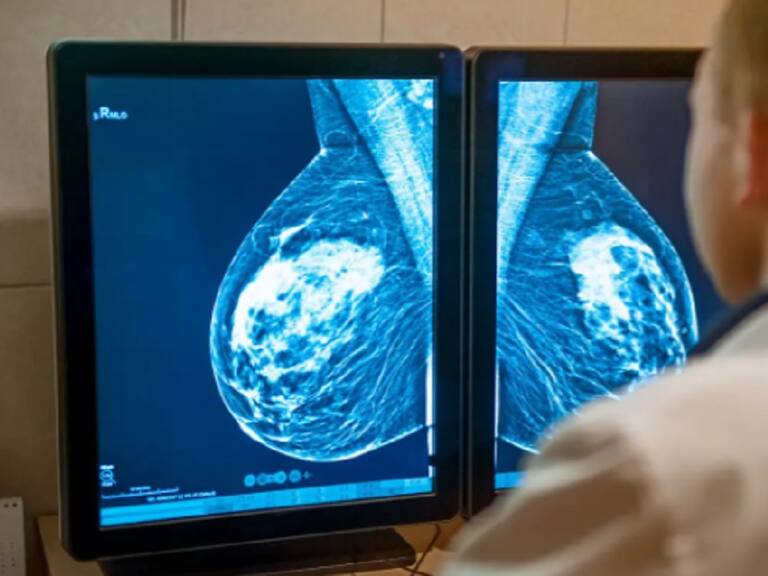

Es un escándalo total, que remece a la región del Biobío. Un reportaje de T13 reveló que 1200 mamografías realizadas por un laboratorio local habrían sido falsificadas.

Y ahí se dieron cuenta que eran 1200 mamografías las que estaban erradas, generando toda una búsqueda de las féminas que, ahora, podrían estar enfermas sin saberlo debido a estos falsos diagnósticos.